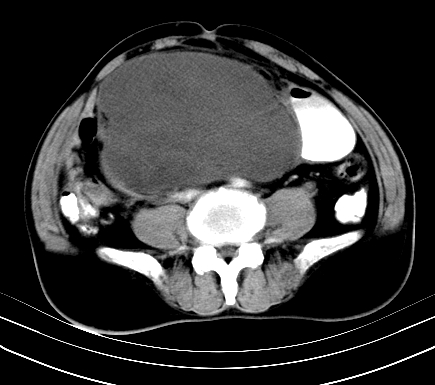

标题: CT19729B:男,74岁,因腿疼就诊,查体触腹部肿物,

增强扫描

动脉期

【ct表现】

1、肿块巨大,往往位于腹膜后,长大后才引起症状而就诊;那么位于腹膜后的肿瘤80%为恶性肿瘤。

2、实性肿瘤,增强扫描轻度不均强化,实性肿瘤一般不是好东西。

3、肿瘤边缘似见少许脂肪样密度。

4、腹膜后未见肿大淋巴结,但肿瘤于临近的肠管及组织接触紧密。

【诊断】

腹部占位,考虑位于腹膜后的恶性肿瘤,脂肪肉瘤(实体型)可能性大。

术后病理结果:腹膜后脂肪肉瘤。